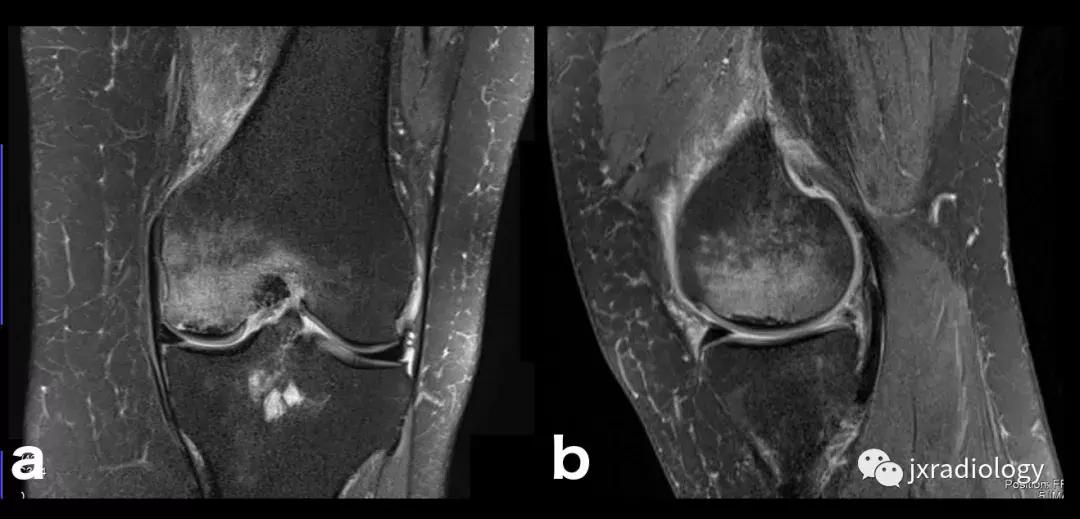

图21:这名患者的炎症性关节炎表现为围绕内侧股 - 胫室侵蚀性改变的骨髓水肿。 它是血管源性骨髓水肿的一个例子(继发于血液和血清传递至骨髓空间毛细血管床)(a,b:冠状T1-WI和PD-FS-WI)。

图22:骨肉瘤(a,b:冠状和轴向PD-FS-WI):肿瘤性水肿继发于骨小梁破坏引起的直接毛细血管损伤,并伴有血管内液体释放和出血。 区分周围水肿和肿瘤侵袭可能是困难的。